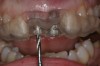

Figure 12  Buccal view of the implants immediately after provisionalization. Even at the temporary stage, the soft tissue closely mimicked the original periodontal drape.

Figure 12

Figure 13  Initial view of this patient depicts the esthetic disharmony and smile imbalance. There was a retained primary maxillary canine on the right, a permanent canine in place of the right lateral incisor, a missing tooth No. 10 replaced with a cantilever restoration, asymmetric gingival margins, recession on tooth No. 11, and uneven incisal edges.

Figure 13